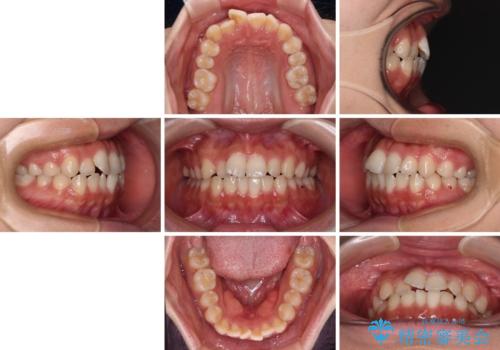

【モニター】短期間で終わりたい ワイヤー装置での非抜歯矯正

- 20代女性

- 1年1ヶ月

- 前歯のデコボコを気にして来院された患者様です。

マウスピース矯正のような自己管理の煩わしさがなく、早く治療を終えたいとのことで、ワイヤー装置による矯正治療を行うこととしました。

当初予定通り、1年で治療を終えることができました。